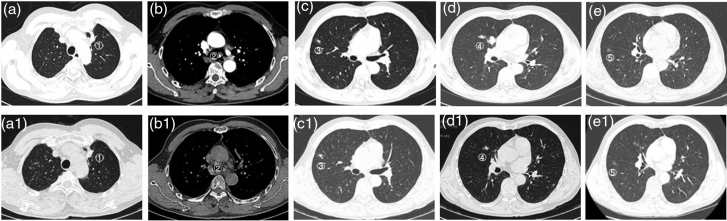

Mesenchymal-epithelial transition factor (MET) exon 14 skipping alterations are rare mutations in non-small-cell lung cancer, associated with high malignancy and poor prognosis. This article presents a case of a patient diagnosed with advanced left upper lung adenocarcinoma characterized by a MET14 skipping mutation. Following first-line treatment with crizotinib, there was a significant reduction in the size of the primary lesion; however, during the course of treatment, an increase in size and prominence of solid components were observed in the right upper lung lesion. A biopsy and subsequent genetic testing revealed an epidermal growth factor receptor L858R mutation in the right upper lung adenocarcinoma, indicating the presence of multiple primary lung cancers. The patient opted against surgical intervention and local treatments, choosing instead a combination therapy regimen that included almonertinib and crizotinib. This treatment approach led to a significant reduction in the size of the right upper lung lesion. The patient's condition has remained stable without any signs of progression, resulting in an overall survival duration exceeding 53 months.